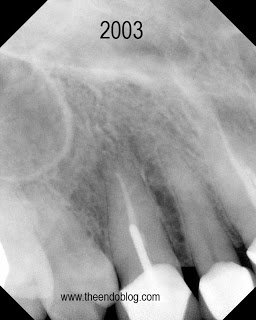

This patient has crowns on #6-#11. Tooth #6 is causing a localized ache, affected by pressure and chewing. #6 is sensitive to percussion with normal probings. DX: Prior RCT with Symptomatic Apical Periodontitis (SAP). The margins are suspicious, but apical surgery was chosen to address the infection w